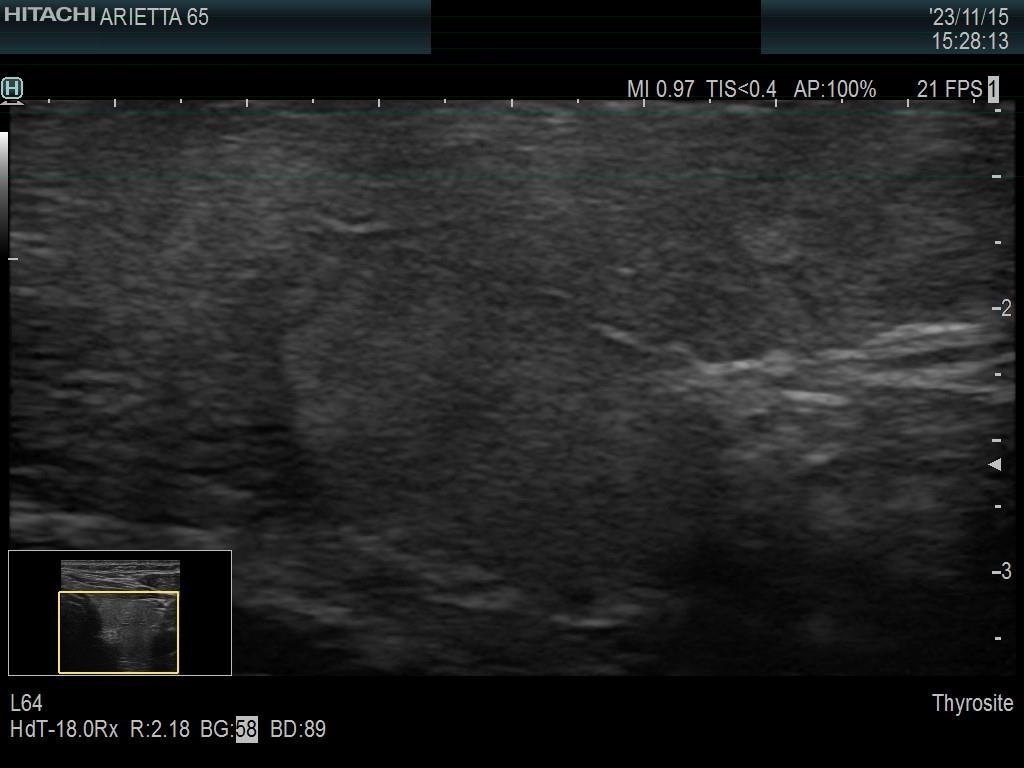

Introduction - case 1407 (ultrasonographic picture 13)

Left lobe, longitudinal scan -

another enlarged view